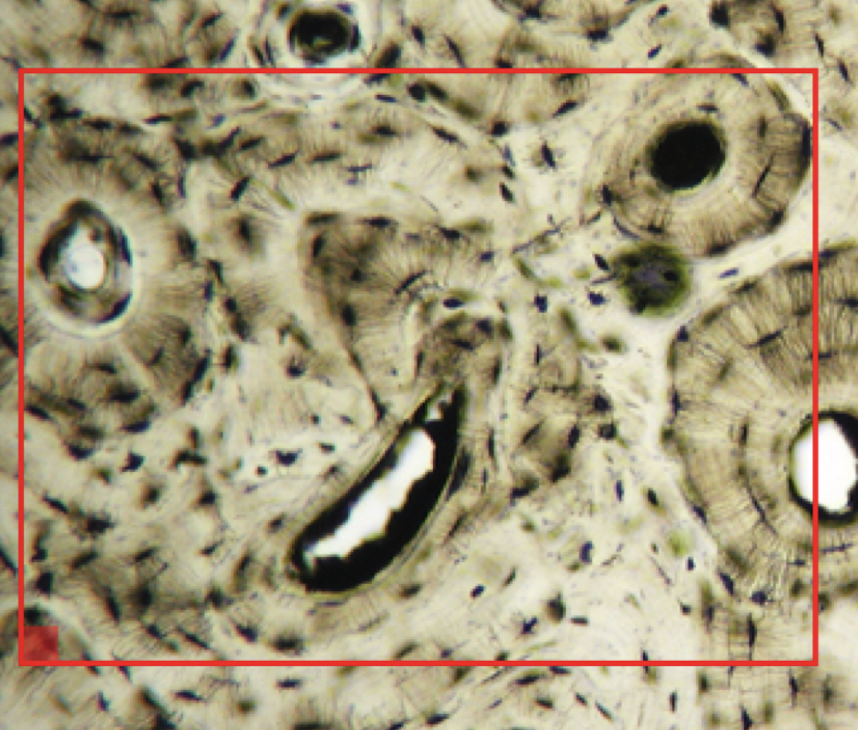

20

ID

Volkmann’s Canal

21

22

Circumferential Lamella

23

Haversian Canal